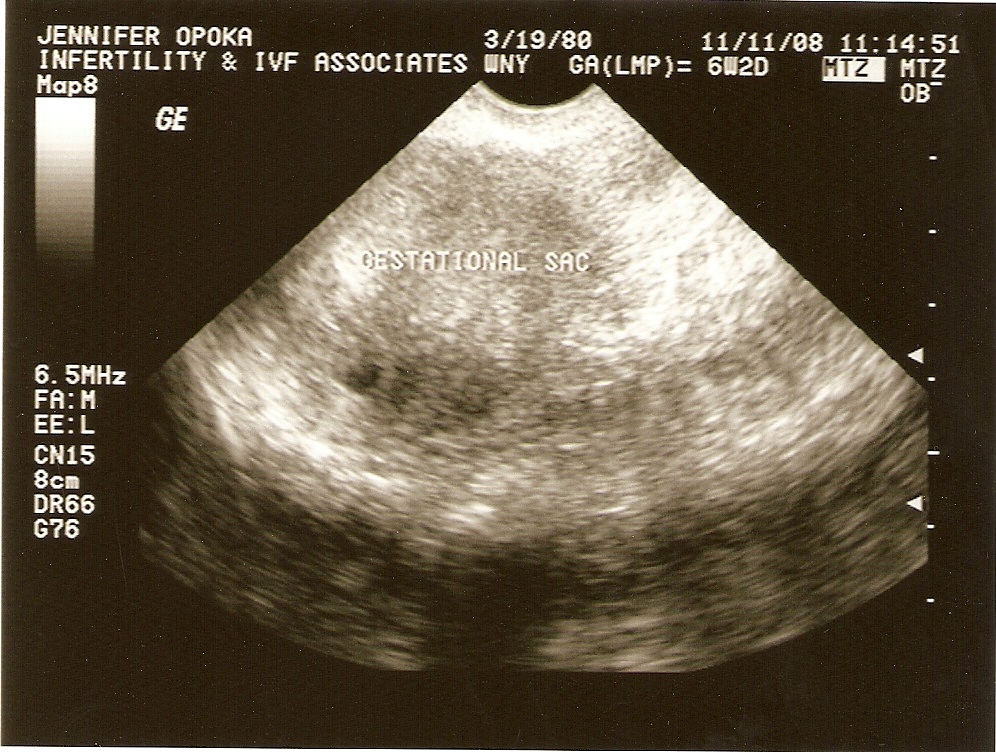

The walk has a special place in my heart, as Mike and I struggled with infertility for over four and a half years. We found out I was pregnant in October 2008 and were ecstatic. At seven weeks, I miscarried due to a partial molar pregnancy. A molar pregnancy is a type of gestational trophoblastic disease (GTD), which is a group of rare tumors that involve abnormal growth of cells in the uterus. Molar pregnancies are rare, occurring in approximately 1 out of every 1,000 pregnancies. With a partial mole, the fetus is overcome by the growing abnormal mass rather quickly. In most cases, a partial mole is fully treated by initial surgery; only about 5% need further treatment. I developed persistent gestational trophoblastic disease, which is not a separate type of GTD, but a term used to describe GTD that is not cured by initial surgery. As a result, I was referred to an Oncologist and had to undergo chemotherapy treatments. Because of the molar pregnancy, Mike and I were not able to try to conceive for one year. Grieving our loss was very difficult, as well as understanding an unusual condition that most people have never heard of. The walk has been a beautiful way for us to honor and remember our baby. I previously served on the walk committee and it was a wonderful way to focus my energy on something positive. In 2012, we were blessed with the birth of our son, Griffin Hansen Opoka. He is our miracle baby and the light of our lives. A true gift from God. We enjoy every minute we spend with Griffin. We never take being parents for granted, as so many people never get that opportunity. Having Griffin has changed our lives immensely, but we will never forget our first gift from God, Baby Opoka. Our angel is in heaven, looking down on us and watching over us. Baby Opoka will always be remembered and forever loved. I would like to thank you in advance for your commitment to join Mike and I and other members of the community walk in memory of our children by donating to the Walk to Remember.